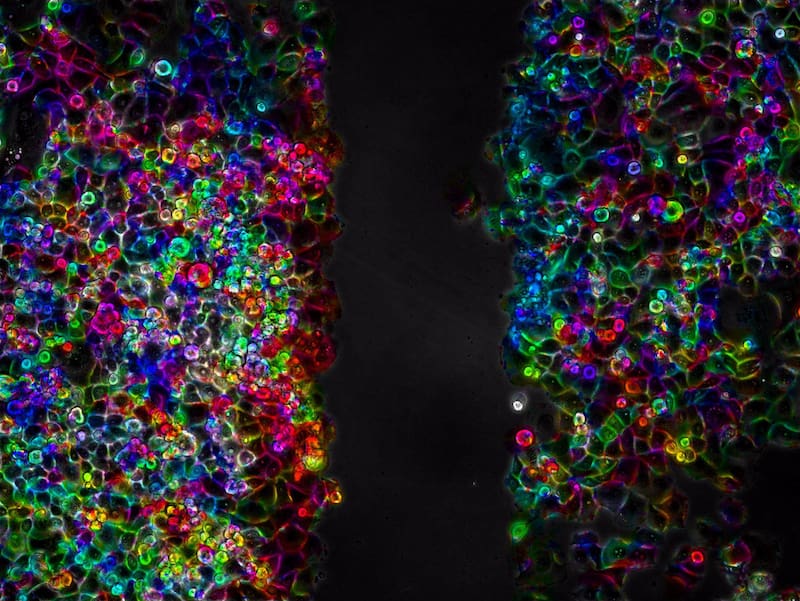

En concreto, los investigadores desarrollaron la investigación sobre muestras ‘in vitro’ de cáncer de páncreas. “Aplicamos una dosis de tan solo veinte minutos de ultrasonidos de baja intensidad sobre muestras de células de cáncer de páncreas PANC-1 y conseguimos parar el avance colectivo e individual de las células en monocapa durante, al menos, dos días”, argumentó la experta.

La aplicación de ondas ultrasónicas en determinadas condiciones acústicas durante 15 o 20 minutos inhibe la capacidad de movimiento celular durante largos periodos de tiempo, de más de 48 horas o incluso hasta 3 días después del tratamiento. Además, los científicos observaron también cierta inhibición en los procesos de proliferación celular que, en la actualidad, analizan en otros experimentos de sus laboratorios.